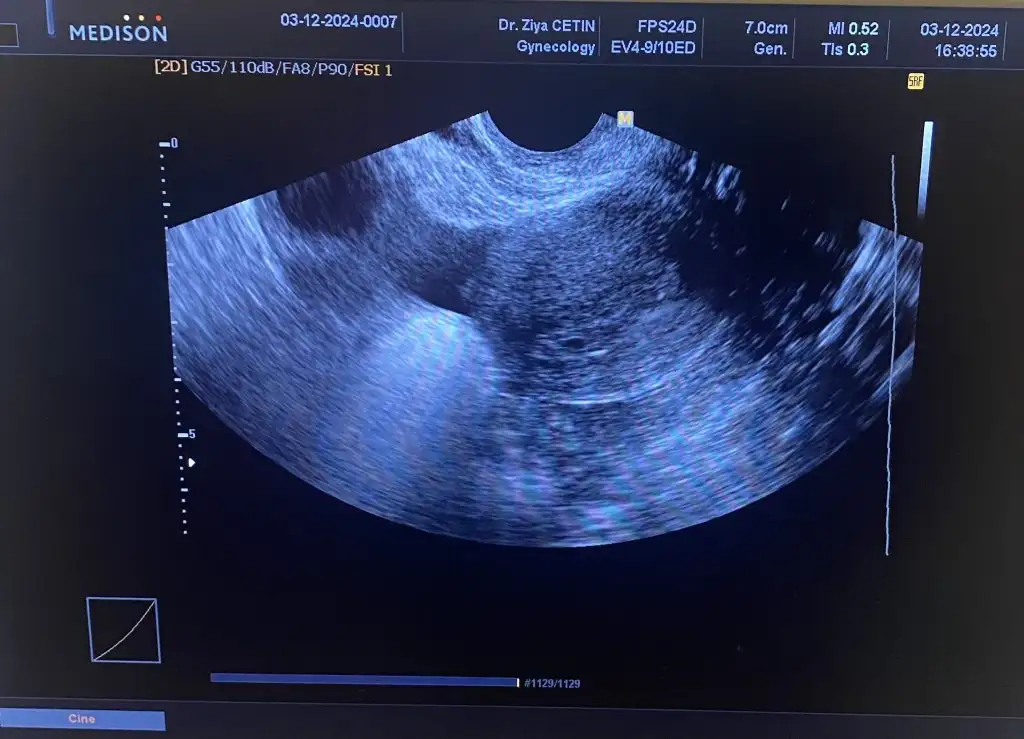

Kızlar kalp atışı için doktora gidiyorummm 6. Haftaya yeni girdik gerçi ama dualarınızı bekliyorummm![]()

Hayırlı haberlerle gel canımKızlar kalp atışı için doktora gidiyorummm 6. Haftaya yeni girdik gerçi ama dualarınızı bekliyorummm![]()

Güzel haberlerle gel canımmmmmmmmmKızlar kalp atışı için doktora gidiyorummm 6. Haftaya yeni girdik gerçi ama dualarınızı bekliyorummm![]()